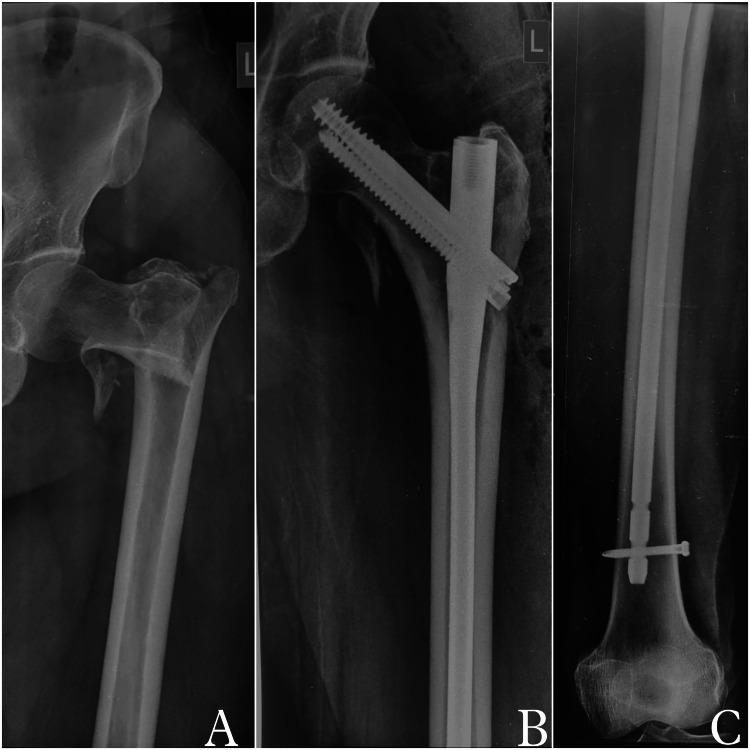

With an increasing life expectancy, there has been an increase in the incidence of intertrochanteric fractures. These fractures in the elderly are disabling and have a tremendous impact on the healthcare system. Despite substantial improvements in implant design and surgical techniques, high failure rates have been observed, varying with the severity of the fracture and the type of fixation. Intramedullary nails have become popular in recent times, especially in unstable fractures. The purpose of the present study is to compare the functional outcomes and complications of long versus short InterTAN cephalomedullary nails (Smith & Nephew, Memphis, Tennessee) used for intertrochanteric fracture fixation.

All patients who had intertrochanteric fractures classifiable as AO OTA (Arbeitsgemeinschaft für Osteosynthesefragen/Orthopaedic Trauma Association) 31-A and were treated with either a short InterTAN nail (SIN) or long InterTAN nail (LIN) between March 2017 and March 2020 were retrospectively assessed. AO subtype A1 fractures are considered to be stable whereas subtype A3 fractures are considered unstable. The stability of subtype A2 fractures is variable depending on the amount of posteromedial comminution. Both stable and unstable fractures were included. Patients aged above 18 years, who had a normal pre-injury gait and were operated on within seven days of trauma as per the records were included in the study. Postoperatively, functional outcome recorded using the modified Harris hip score (mHHS) was compared. The minimum follow-up period was 24 months.

A total of 89 patients fulfilling the inclusion criteria were included. The mean age was 67.5 ± 8.92 years. Of the patients, 72% were above 60 years of age and 68% of those were females. The mean follow-up period was 31 months (range: 24-54 months). Of the patients, 84.27% sustained fractures after a trivial trauma due to slip and fall at home. All fractures had united at nine to 12 months, except one had a screw cut-out, which required revision surgery. The mean mHHS at three months and nine to 12 months postoperatively was 42.46 ± 3.62 and 87.24 ± 6.44, respectively. The patients who were treated with LIN had a significantly better functional outcome at three-month follow-up (p-value < 0.05); however, post one year, this effect plateaued and no significant difference was seen when comparing SIN with LIN. The results also showed that there was no significant difference in complications among SIN and LIN.

Both LIN and SIN are equally effective for the surgical management of intertrochanteric fractures, and have similar functional outcomes. SIN, however, has shorter surgical procedure time and lesser estimated blood loss. LIN allowed in early recovery evidenced by better Harris hip scores at three months duration, thus improving the quality of life in the initial months post surgery. The choice of implant should be individualized according to fracture anatomy, patients' needs and expectations, and surgeons' expertise.